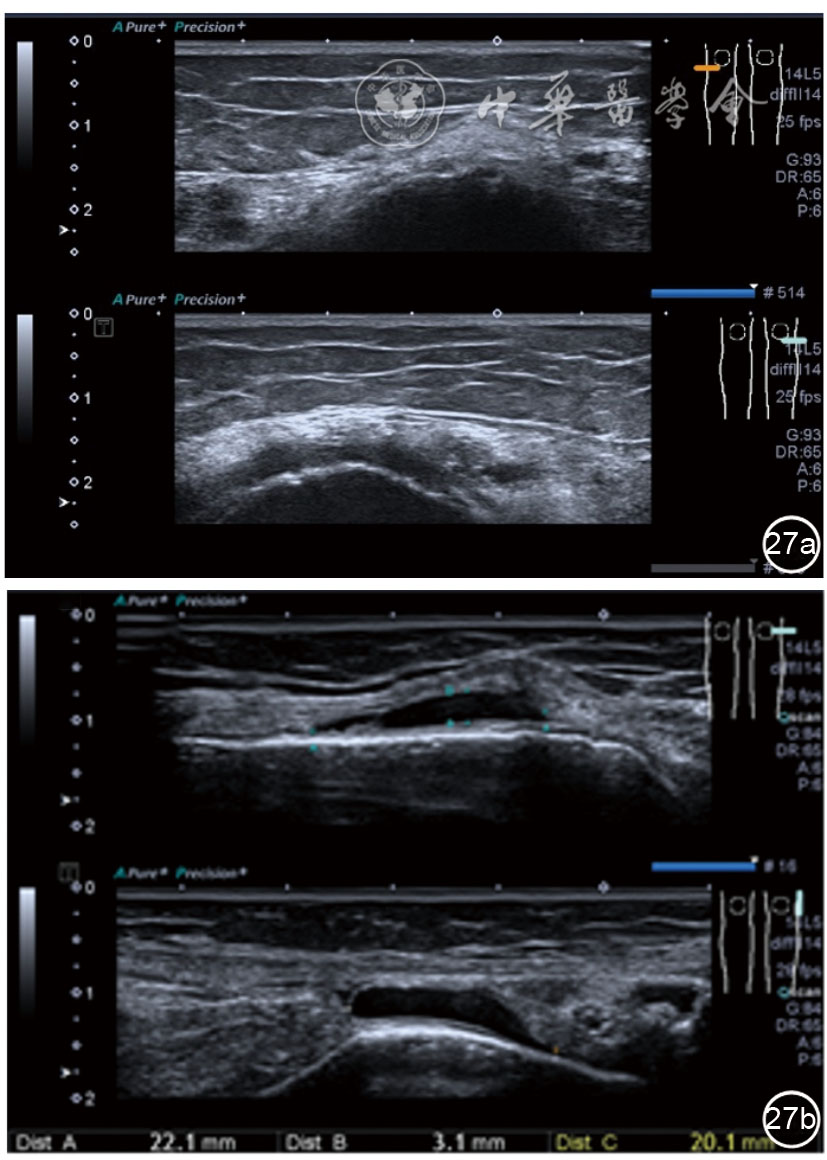

髂胫束的最佳显示切面为长轴切面,采用高频探头,扫查深度<3 cm。超声表现胫骨附着点处骨皮质不规则,髂胫束增厚,回声减低,其周围组织水肿,血流增加(图26)。股骨髁部肿胀、增厚,回声减低,超声触诊可能诱发股骨外侧髁处的疼痛。部分患者可见髂胫束滑囊扩张,内为无回声积液(图27)。

图27 超声图像显示股骨髁部肿胀、增厚,回声减低,部分患者可见髂胫束滑囊扩张